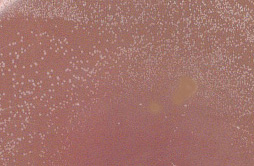

La culture sur gélose au sang frais et celle au sang cuit est, en revanche, positive. Voici l'aspect après 24 heures d'incubation à 37°C en aérobiose :